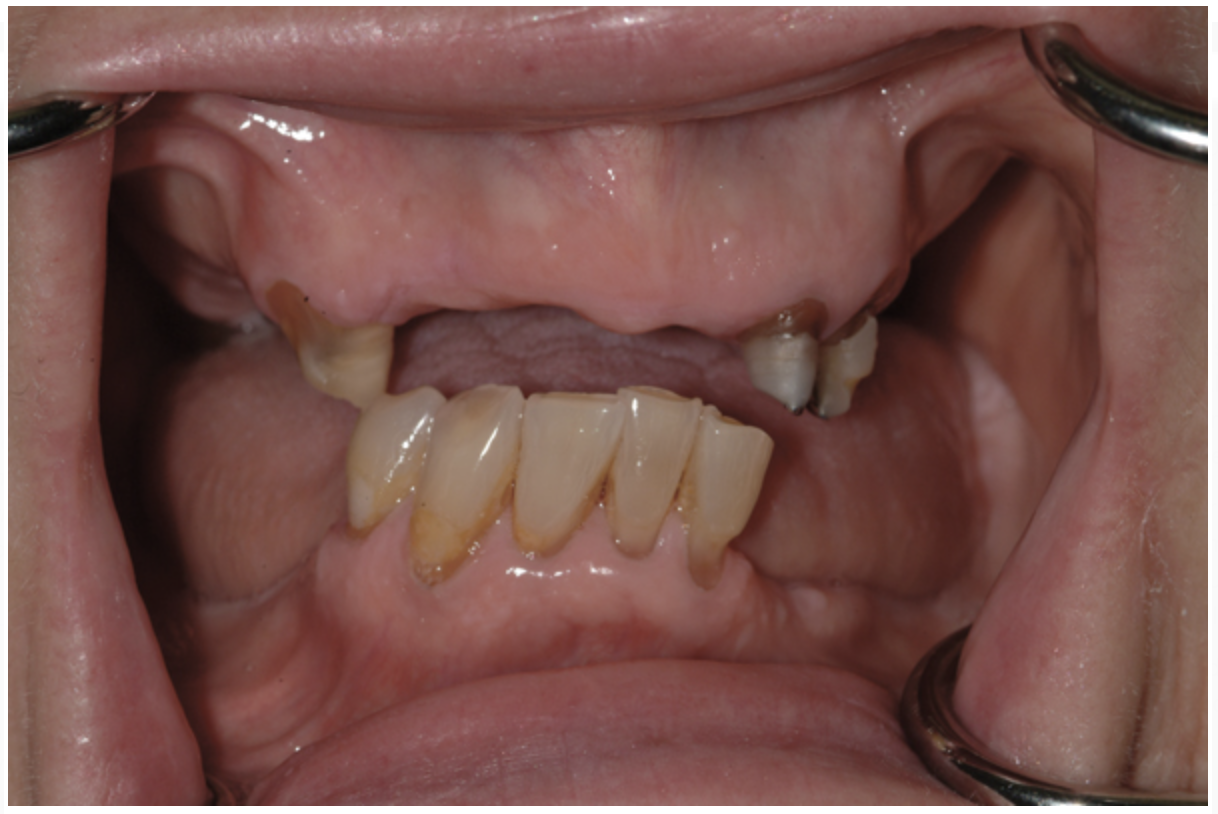

Fig 18. The patient’s intraoral condition.

Figure 18

Dental rehabilitation with the All-on-4 treatment concept is often a life-changing event for edentulous and terminal dentition patients that results in unprecedented quality of life improvements (Figure 17 through Figure 20).